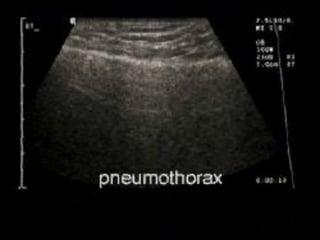

7. Diagnosis of pneumothorax

Absent lung sliding

Exaggerated horizontal artifacts

Loss of comet-tail artifacts

Broadening of the pleural line to a band

The key sonographic signs of

Pneumothorax

 Multiple studies have shown ultrasound to be more

sensitive than supine CXR for the detection of

pneumothorax.

 Sensitivities ranged from 86-100% with specificities from

92-100%.

 Furthermore USS can be performed more rapidly at the

bedside.

 Detection with ultrasound relies on the fact that free air is

lighter than normal aerated lung tissue, and thus will

accumulate in the nondependent areas of the thoracic

cavity. (ie anteriorly when patient is supine).

himaP  Multiple studieshave shown ultrasound to be more sensitive than supine CXR for the detection of pneumothorax.  Sensitivities ranged from 86-100% with specificities from 92-100%.  Furthermore USS can be performed more rapidly at the bedside.  Detection with ultrasound relies on the fact that free air is lighter than normal aerated lung tissue, and thus will accumulate in the nondependent areas of the thoracic cavity. (ie anteriorly when patient is supine).

To get thelung window  Patient should be supine.  Use high frequency linear array or a phased array transducer.  Position in the midclavicular line, 3rd to 4th intercostal space with probe oriented longitudinally.  Position between ribs.